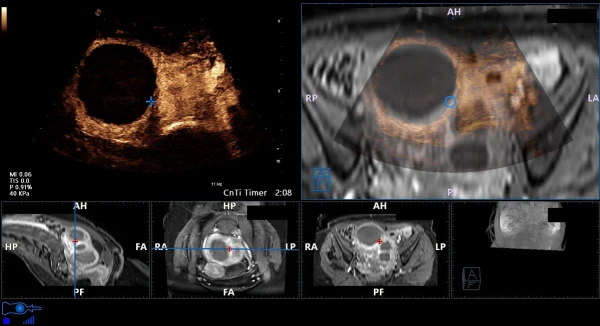

Maqsadli biopsiya uchun avtomatik ro'yxatga olish bilan prostata bezining MRI / ultratovush tasvirlarini segmentatsiyalash;

Ko'krak MRG. 3D modelga asoslangan ultratovush tekshiruvi ma'lumotlari bilan real vaqt rejimida ko'krak va termoyadroviy MRI tasvirlarini segmentatsiyalash;